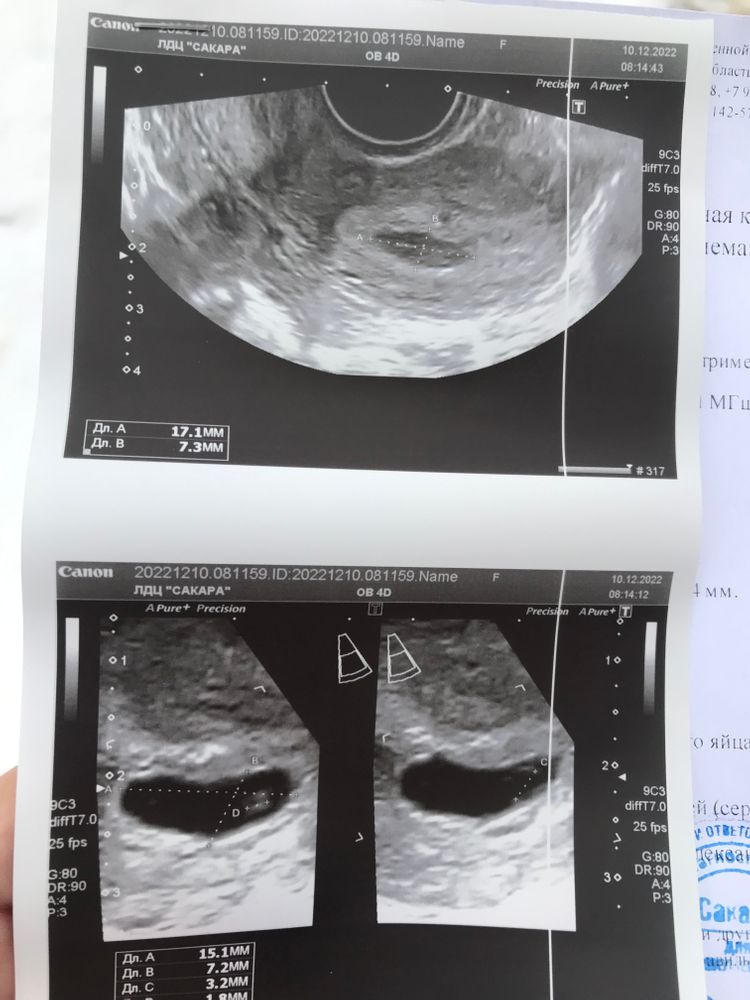

Сикирина Ольга, ходила сегодня. Эмбрион появился, сердечко пока не слышно, сказали через недельку сходить еще. Но увидели отслойку, про которую в больнице мне ничего не сказали… узист сказала пить утержестан (что я и так делаю), и побольше отдыхать.